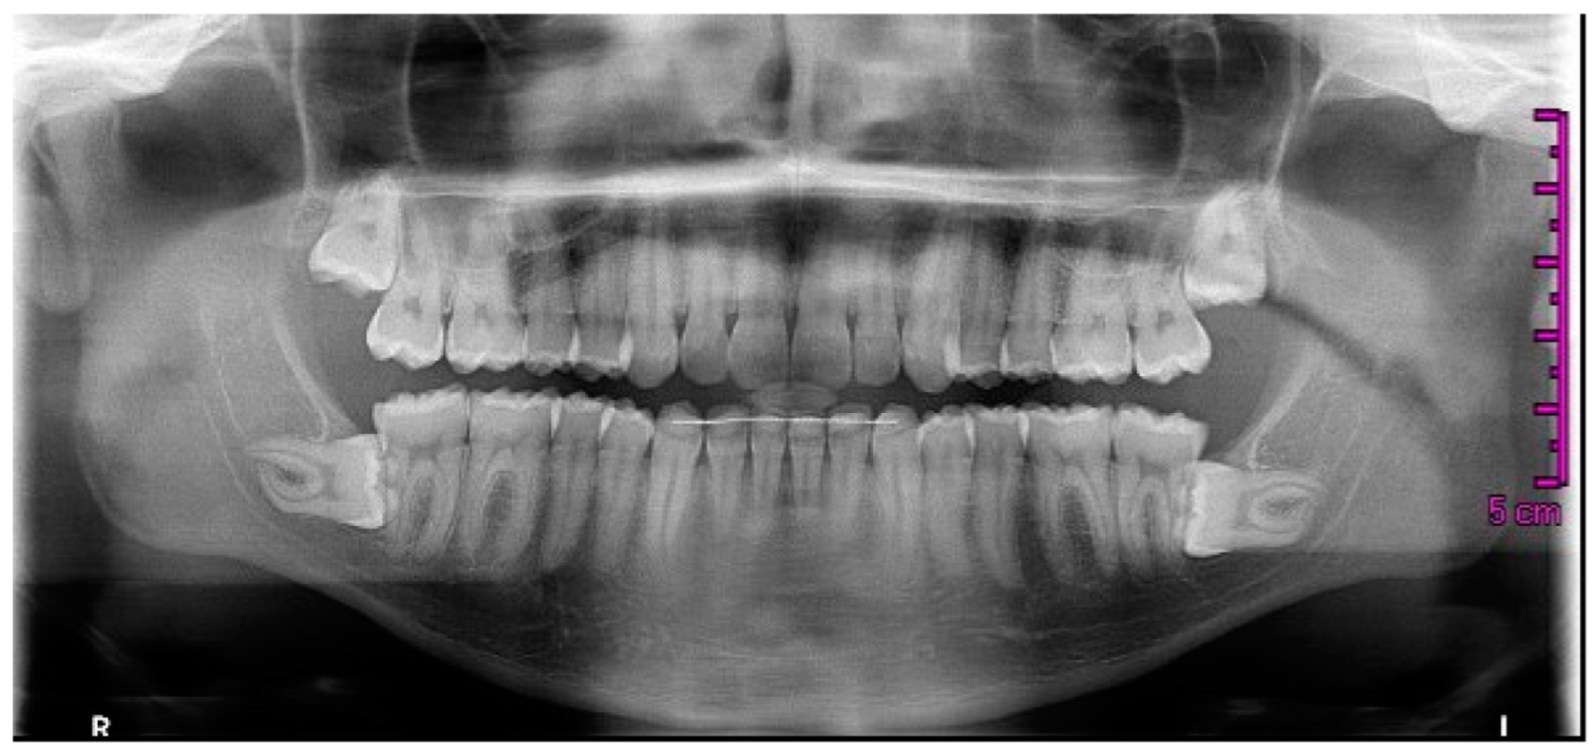

Orthopantomography (OPG) is the preferred imaging method for initial evaluation, offering a panoramic view of dental arches and adjacent structures (Figure 1). OPG combines low-radiation exposure with patient comfort. Computed tomography (CT) with specialized software may provide three-dimensional analyses for more complex cases (Figure 2).

Figure 1. Panoramic X-ray of the dentition and jaw using orthopantomography (OPG).

The imaging modalities used, orthopantomography (OPG) and cone beam computed tomography (CBCT), represent standard practices for assessing third molar impactions and their associated periodontal impacts. OPG provides a convenient and low-radiation panoramic view, CBCT offers enhanced three-dimensional imaging crucial for evaluating anatomical proximity and predicting surgical complications. However, these methods have limitations, such as OPG’s two-dimensional representation and CBCT radiation exposure [30].